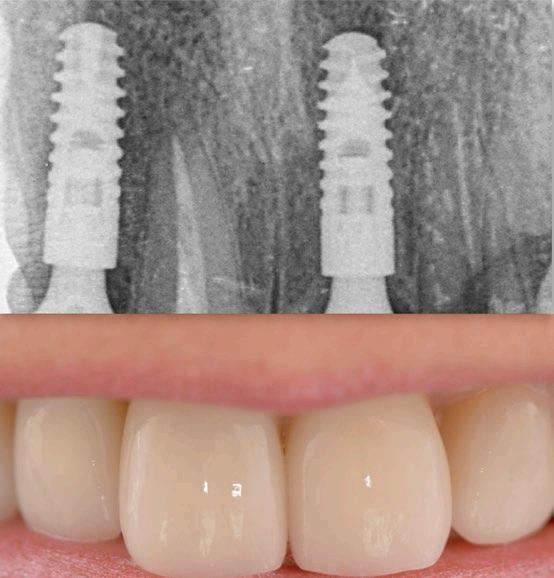

Jak už bylo dříve zmíněno, diagnostická fáze hraje zásadní roli, a proto musí být provedena s maximální

pečlivostí. Zahrnuje nejen posouzení stavu jednotlivých zubů, ale také analýzu rizikových faktorů spojených s celkovým zdravotním stavem a životním stylem pacienta. Pro ilustraci této problematiky ukazují obrázky 1.1 a 1.2 diagnosticko-terapeutický postup, který navrhuje možné léčebné řešení a aktivně zapojuje pacienta do rozhodovacího procesu. Tento přístup zajišťuje, že je pacient plně informován o dostupných terapeutických možnostech, což mu umožňuje činit kvalifikovaná rozhodnutí o svém orálním zdraví.